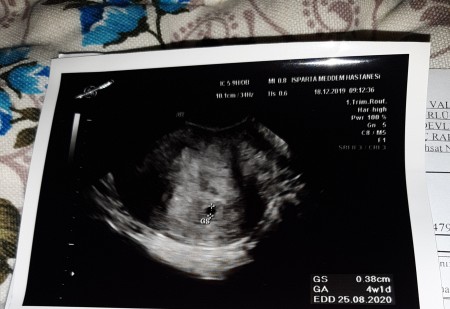

Hamile ya da değil çarpıntı herkeste görülebilir. Karından ultrasonda bebeğin kalp atışı en erken 5 6 hafta arasında bir buçuk aylık görülebilir. Bebeğin kalp atışı hangi haftada belli olur anne adaylarının en çok merak ettiği sorulardan birisidir. Haftada ultrason muayenesi 3 yanıt gebelik kaybı 6 yanıt vücutta kaşınma 3 yanıt clexane iğne 17 yanıt i̇ki dişim apse yapti allah riza icin yardımcı olun 5 yanıt dış gebelik tedavisinde sancı ve kanama olur mu.

Stres özellikle gebeliğin ilk trimesterin ilk üç ay de hem anne adayı için hem de bebek için oldukça zararlıdır. Haftasında bebeğin kalp atışları belli olur ve transvajinal ultrason alttan ultrason ile görülebilir doppler ultrason ile duyulabilir.